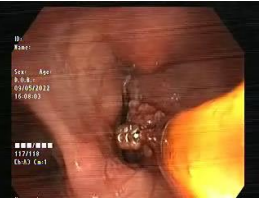

Figures 1,2,3,4

Figure 1